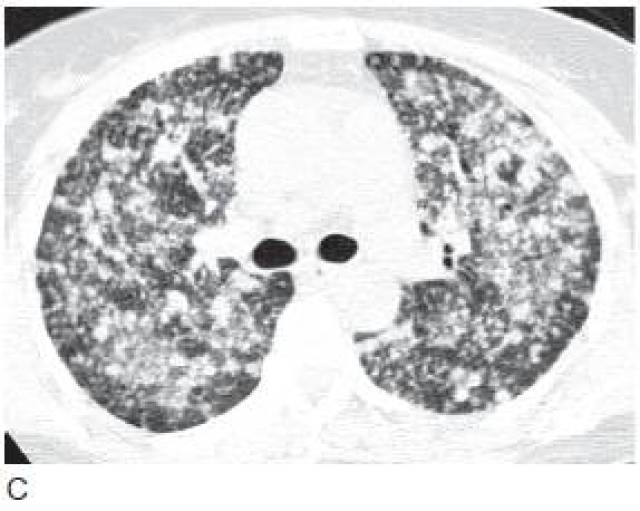

弥漫性肺癌

弥漫性肺癌,弥漫性肝癌

5类肺癌的影像学表现(多图)